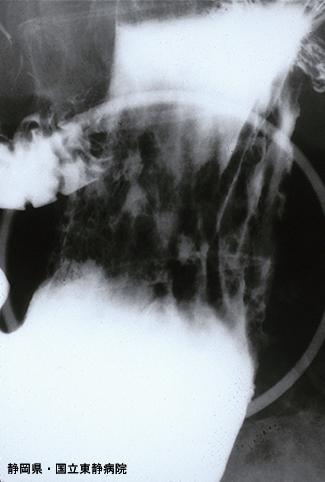

症例提示(所在地,施設名等): 静岡県・ 静岡医療センター ( Dr.尾関ら)

圧迫像でも胃体部から幽門前部にかけて、浅い不整陥凹が多数見られます。(また、他のX線写真で同様の病巣が噴門および穹窿部に至るまで多発していました)

疾患(病理主体)の分類悪性上皮性腫瘍/印環細胞癌

部位(臓器別)胃(部位)/2つ以上

検査方法X-P

多発腫瘍(同一臓器)有(同時性)